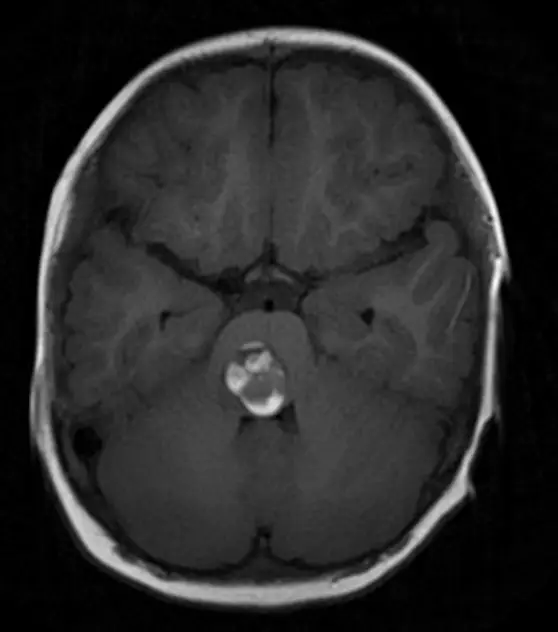

位于大脑核心区域第三脑室的巨大肿瘤,由INC巴特朗菲教授主刀...

18岁男性患者鹏鹏在校期间持续7天出现头晕症状,经检查确诊为...